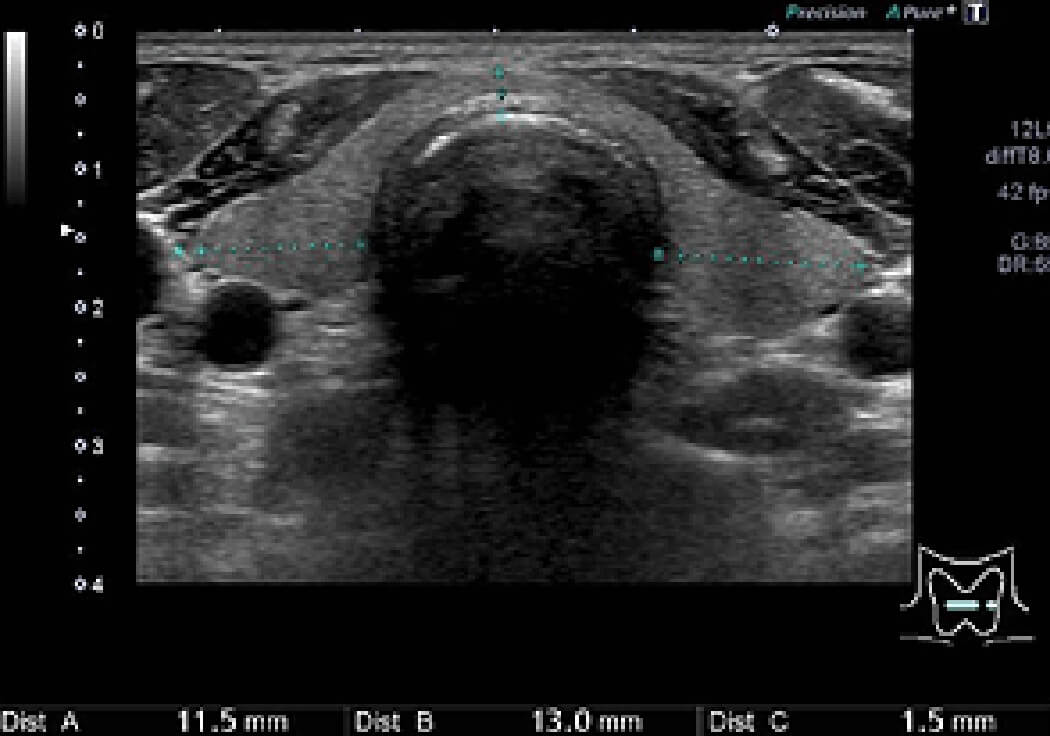

正常甲状腺

甲状腺腫瘤の例